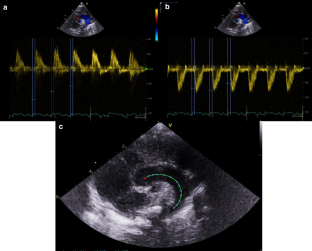

This study is part of a prospective cohort study including monochorionic twins from January 2019. Transthoracic echocardiography was performed within one week after birth. Z-scores for cardiac valve annuli diameters and left ventricle dimensions based on gestational age at birth were compared between smaller and larger twins. Z-score differences between birth weight and cardiac structure per twin were tested against the intercept.